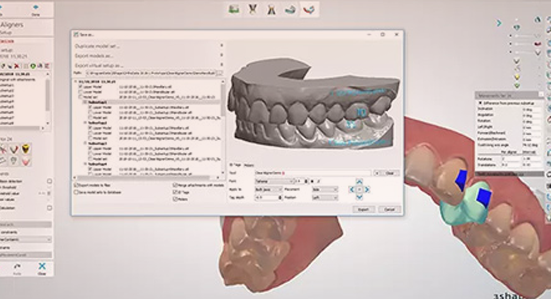

- 搭配数字化智能系统

- 数字化口内扫描技术,3分钟完成数字采集,5分钟预知矫正效果,矫牙效果所见即所得。

通过计算机辅助技术可以准确“预估”矫正效果。托槽均为个性化定制,可与直丝匹配使每颗牙齿按照既定的排牙设计移动到最终理想的位置,让矫正没有白走的路,每一步都算数!